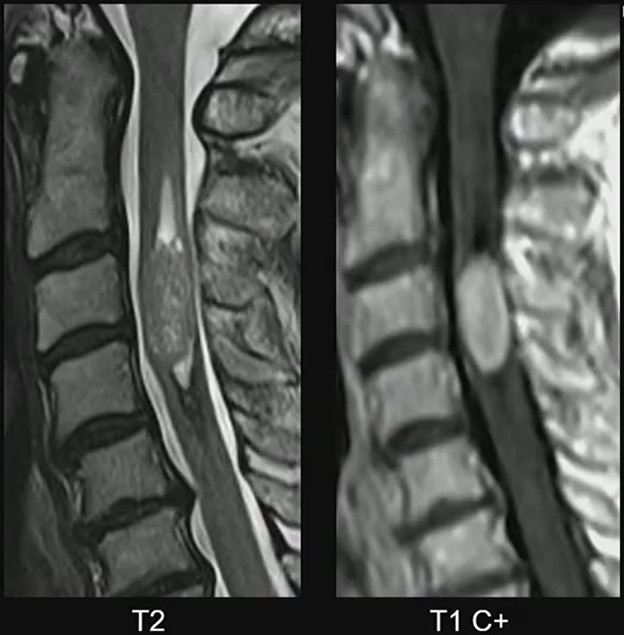

MRI Clues: In Dr. Lall’s case, the lesion demonstrates several classic characteristics:

• Expansile intramedullary mass

• Heterogeneously T2 hyperintense signal

• Enhancing solid components

• Well-demarcated margins

• Short-segment spinal cord involvement

These features support the diagnosis of spinal ependymoma. The well-circumscribed margins are particularly helpful, reflecting the tumor’s relatively defined growth pattern compared with more infiltrative pediatric spinal tumors.